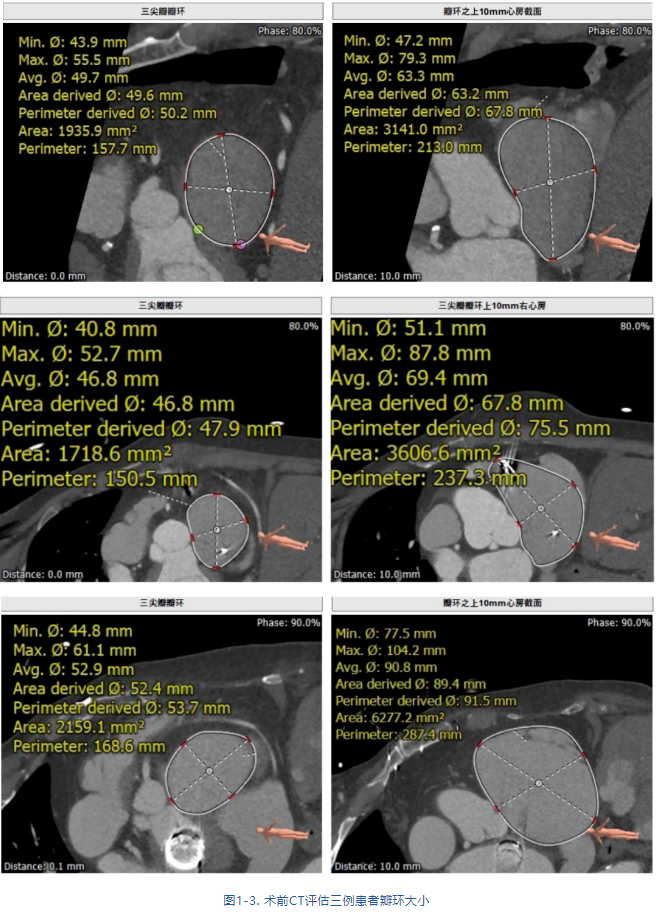

接受治療的是三例重度三尖瓣反流患者,術(shù)前基礎(chǔ)疾病多,均患有嚴重心律失常,其中兩例患者NYHA心功能Ⅱ/Ⅲ級。結(jié)合術(shù)前CT評估結(jié)果,三例患者的自體瓣環(huán)都較大(圖1-3),最大者平均瓣環(huán)為53.7mm;有一例患者有起搏器植入史,術(shù)中操作有纏繞起搏器導線的風險;三例患者入路血管均無嚴重迂曲和鈣化。經(jīng)術(shù)前討論分析,潘湘斌教授及其團隊潘家華教授、朱達教授、王首正教授以及心超室的駱志玲教授,董念國教授及其團隊謝明星教授、尚小珂教授、陳澍教授、鐘禹成教授經(jīng)過討論決定,采用創(chuàng)新的 LuX-Valve Plus經(jīng)血管三尖瓣置換系統(tǒng)對患者進行手術(shù)。LuX-Valve Plus是我國自主研發(fā)的經(jīng)血管介入三尖瓣置換系統(tǒng),經(jīng)頸靜脈入路的微創(chuàng)方式可進一步降低對患者的創(chuàng)傷。